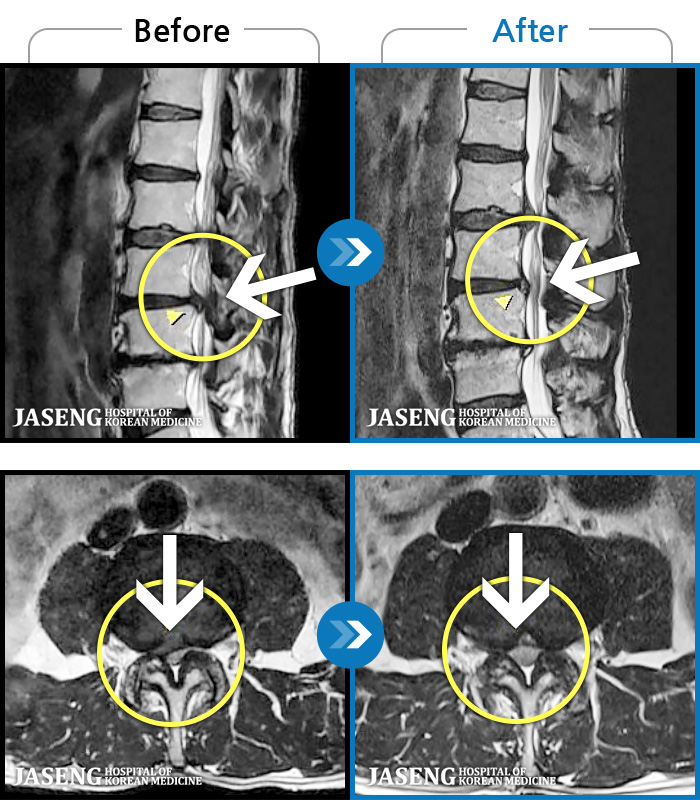

ȯںп Ǹ ǿ ԿǾ, ο ġ ۿ Ƿ ġḦ Ͻñ ٶϴ.